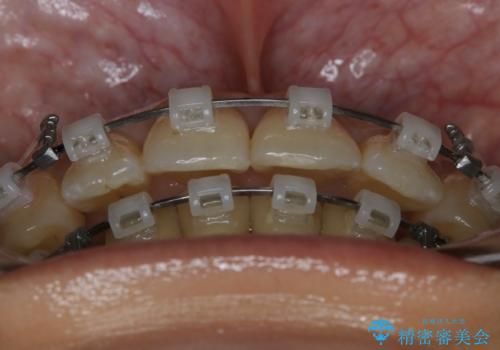

前歯を後ろに下げたい ワイヤー矯正(クリア装置)

- 矯正装置

- クリア装置

抜歯を行うことで前歯を後ろへ下げるスペースを獲得し、口元の突出感や歯のガタつきを改善していきました。